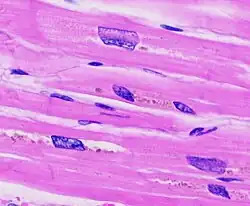

Histopathology of (a) normal myocardium and (b) myocardial hypertrophy. Scale bar indicates 50 μm.

Rectangular "Boxcar" nuclei is a microscopic sign indicating myocardial hypertrophy.